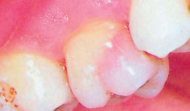

Buccal Bifurcation Cyst | 36, 46 Buccal (兩側 1/3) | 5-13y | - |

![]() |